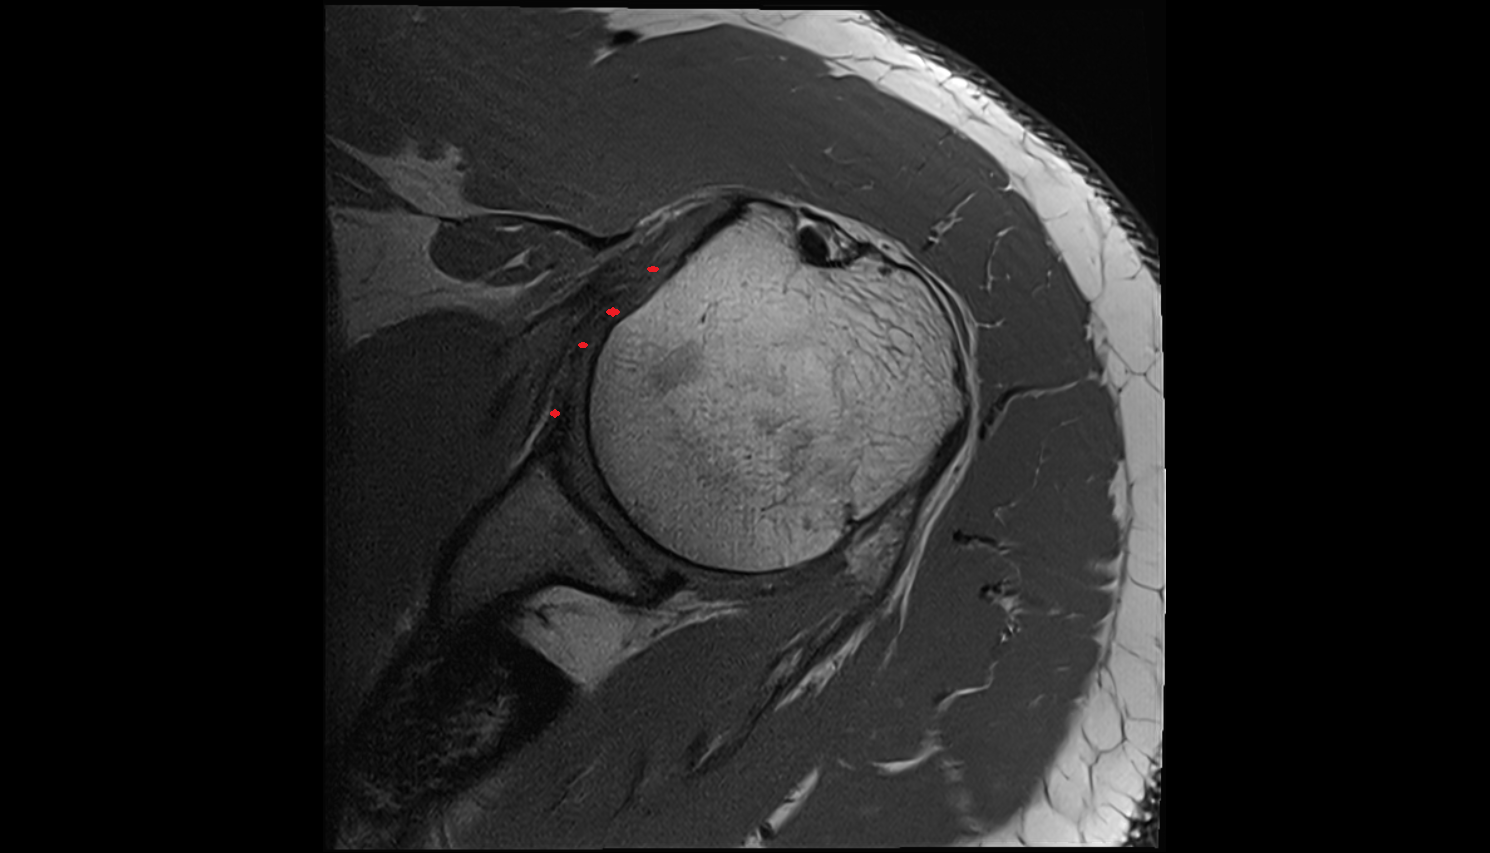

- Glenoid fossa

- Head of humerus

- Glenoid labrum

- Shoulder joint (glenohumeral joint)